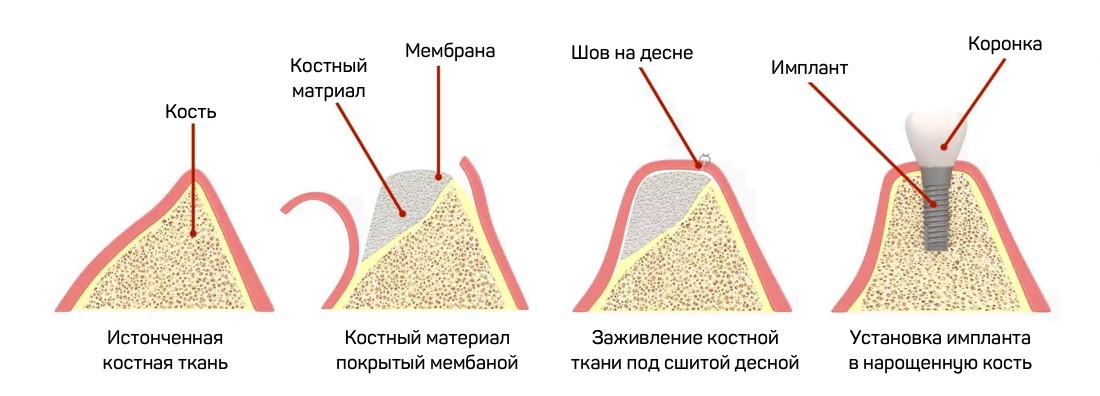

Фото и примеры имплантации зубов при пародонтите

Раздел: Необычные решения